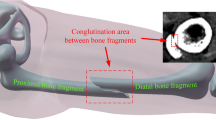

Fractured bone tissue is more difficult to identify because it has some additional features to be considered. Due to the fact that bone fragments may have arbitrary shape and can belong to any bone in a nearby area, it is necessary to label all the fragments during the segmentation process. In some cases, this labelling requires expert knowledge. In addition, a priori knowledge can not be easily used because it is uncommon to find two identical fractures and therefore it is difficult to predict the shape of the bone fragments, specially in comminuted fractures. On the other hand, bone fragments are not completely surrounded by cortical tissue, since they have areas on the edges without cortical tissue due to the fracture. Finally, proximity between fragments and the resolution of the CT image may cause that different fragments appear together as one in the image. For this reason, smoothing filters should be used with caution. This type of filters can deform the shape of bone fragments and fracture zones or even remove small bone fragments. In some cases, it is necessary to detect the fracture zone of each fragment after its segmentation. The fracture zone is the area of the bone where the fracture occurs and is composed of trabecular tissue (Fig. 2). In situations in which bone fragments appear connected, it is difficult to accurately identify the fractured zone of each fragment. Therefore, post-processing can be necessary to delimit fracture zones in these situations.

Transverse, oblique and spiral fractures (Fig. 4b, c,d,e, and f) can be similarly treated during the segmentation. Despite of having different fracture lines, these types of fracture generate two fragments with similar shape. Labelling is necessary, but expert knowledge is not required. Segmentation methods that can be applied depend on whether or not there is displacement. If there is no displacement (Fig. 4c, d, e, and f), they can be processed as a greenstick fracture but considering that there are two fragments. These two fragments can be completely joined, hence an additional processing to separate them may be required. In order to detect fracture zones, the same issues applicable to greenstick fractures should be considered. In the case that there is displacement (Fig. 4b), the probability that both fragments are jointly segmented decreases and methods based on prior knowledge are almost discarded. In return, the fracture zone is easier to be identified. Avulsed fractures normally occur near a join thus the fracture zone is composed almost exclusively by trabecular tissue and the boundaries of the fragments are weak. This complicates the identification of the fracture zone because practically the entire fragment is surrounded by trabecular tissue. Segmental fractures are simple fractures that generate three bone fragments. Therefore, they can be treated as transverse or oblique fractures but considering that there are two distinct fracture regions. Comminuted fractures (Fig. 5) add some additional constraints, hence this is the type of fracture that is more complicated to be segmented. Comminuted fractures usually generate small fragments and bone may be deformed due to the fracture. This is because comminuted fractures are usually associated with crush injuries. In most cases, some fragments overlap in the CT image and require additional processing to be separated. Labelling is necessary and expert knowledge is strongly required to identify fragments. The detection of fracture zones is complicated in this case. Due to the complexity of the fracture, several fracture zones are generated. Since the relationship between fragments in this type of fractures is many-to-many, it can be necessary not only to identify fracture zones, but also to delimit which part of the fracture zone corresponds to each fragment. As mentioned before, some fragments can overlap due to the fracture and therefore post-processing and expert knowledge can be required to accurately identify fracture zones.